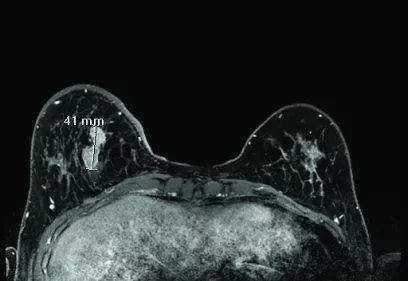

UC Radiology cover

UC Radiology Newsletter

A collaboration of 5 UC Radiology Departments.

Read latest issue